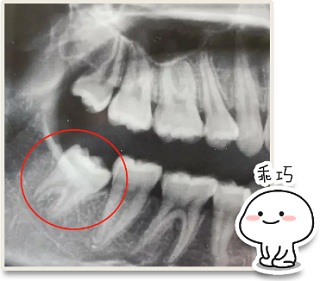

但更多人的智齿都是「卧龙凤雏」

不仅不松动

还长在牙龈里面 + 横行霸道

这样的

甚至这样的

这玩意儿拔出来创伤就大了!